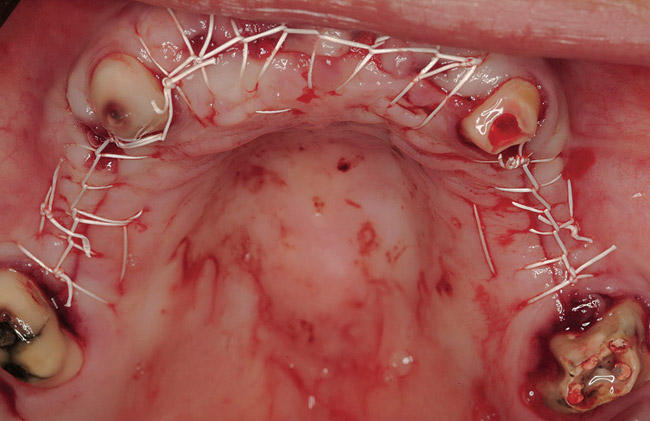

Figure 1  Note wide flap reflection necessary for titanium mesh removal and implant placement. The apical extent of the flap is necessary not only to remove the mesh but also two fixation screws that need to be placed at a safe distance from the apices of the adjacent teeth.

Figure 1